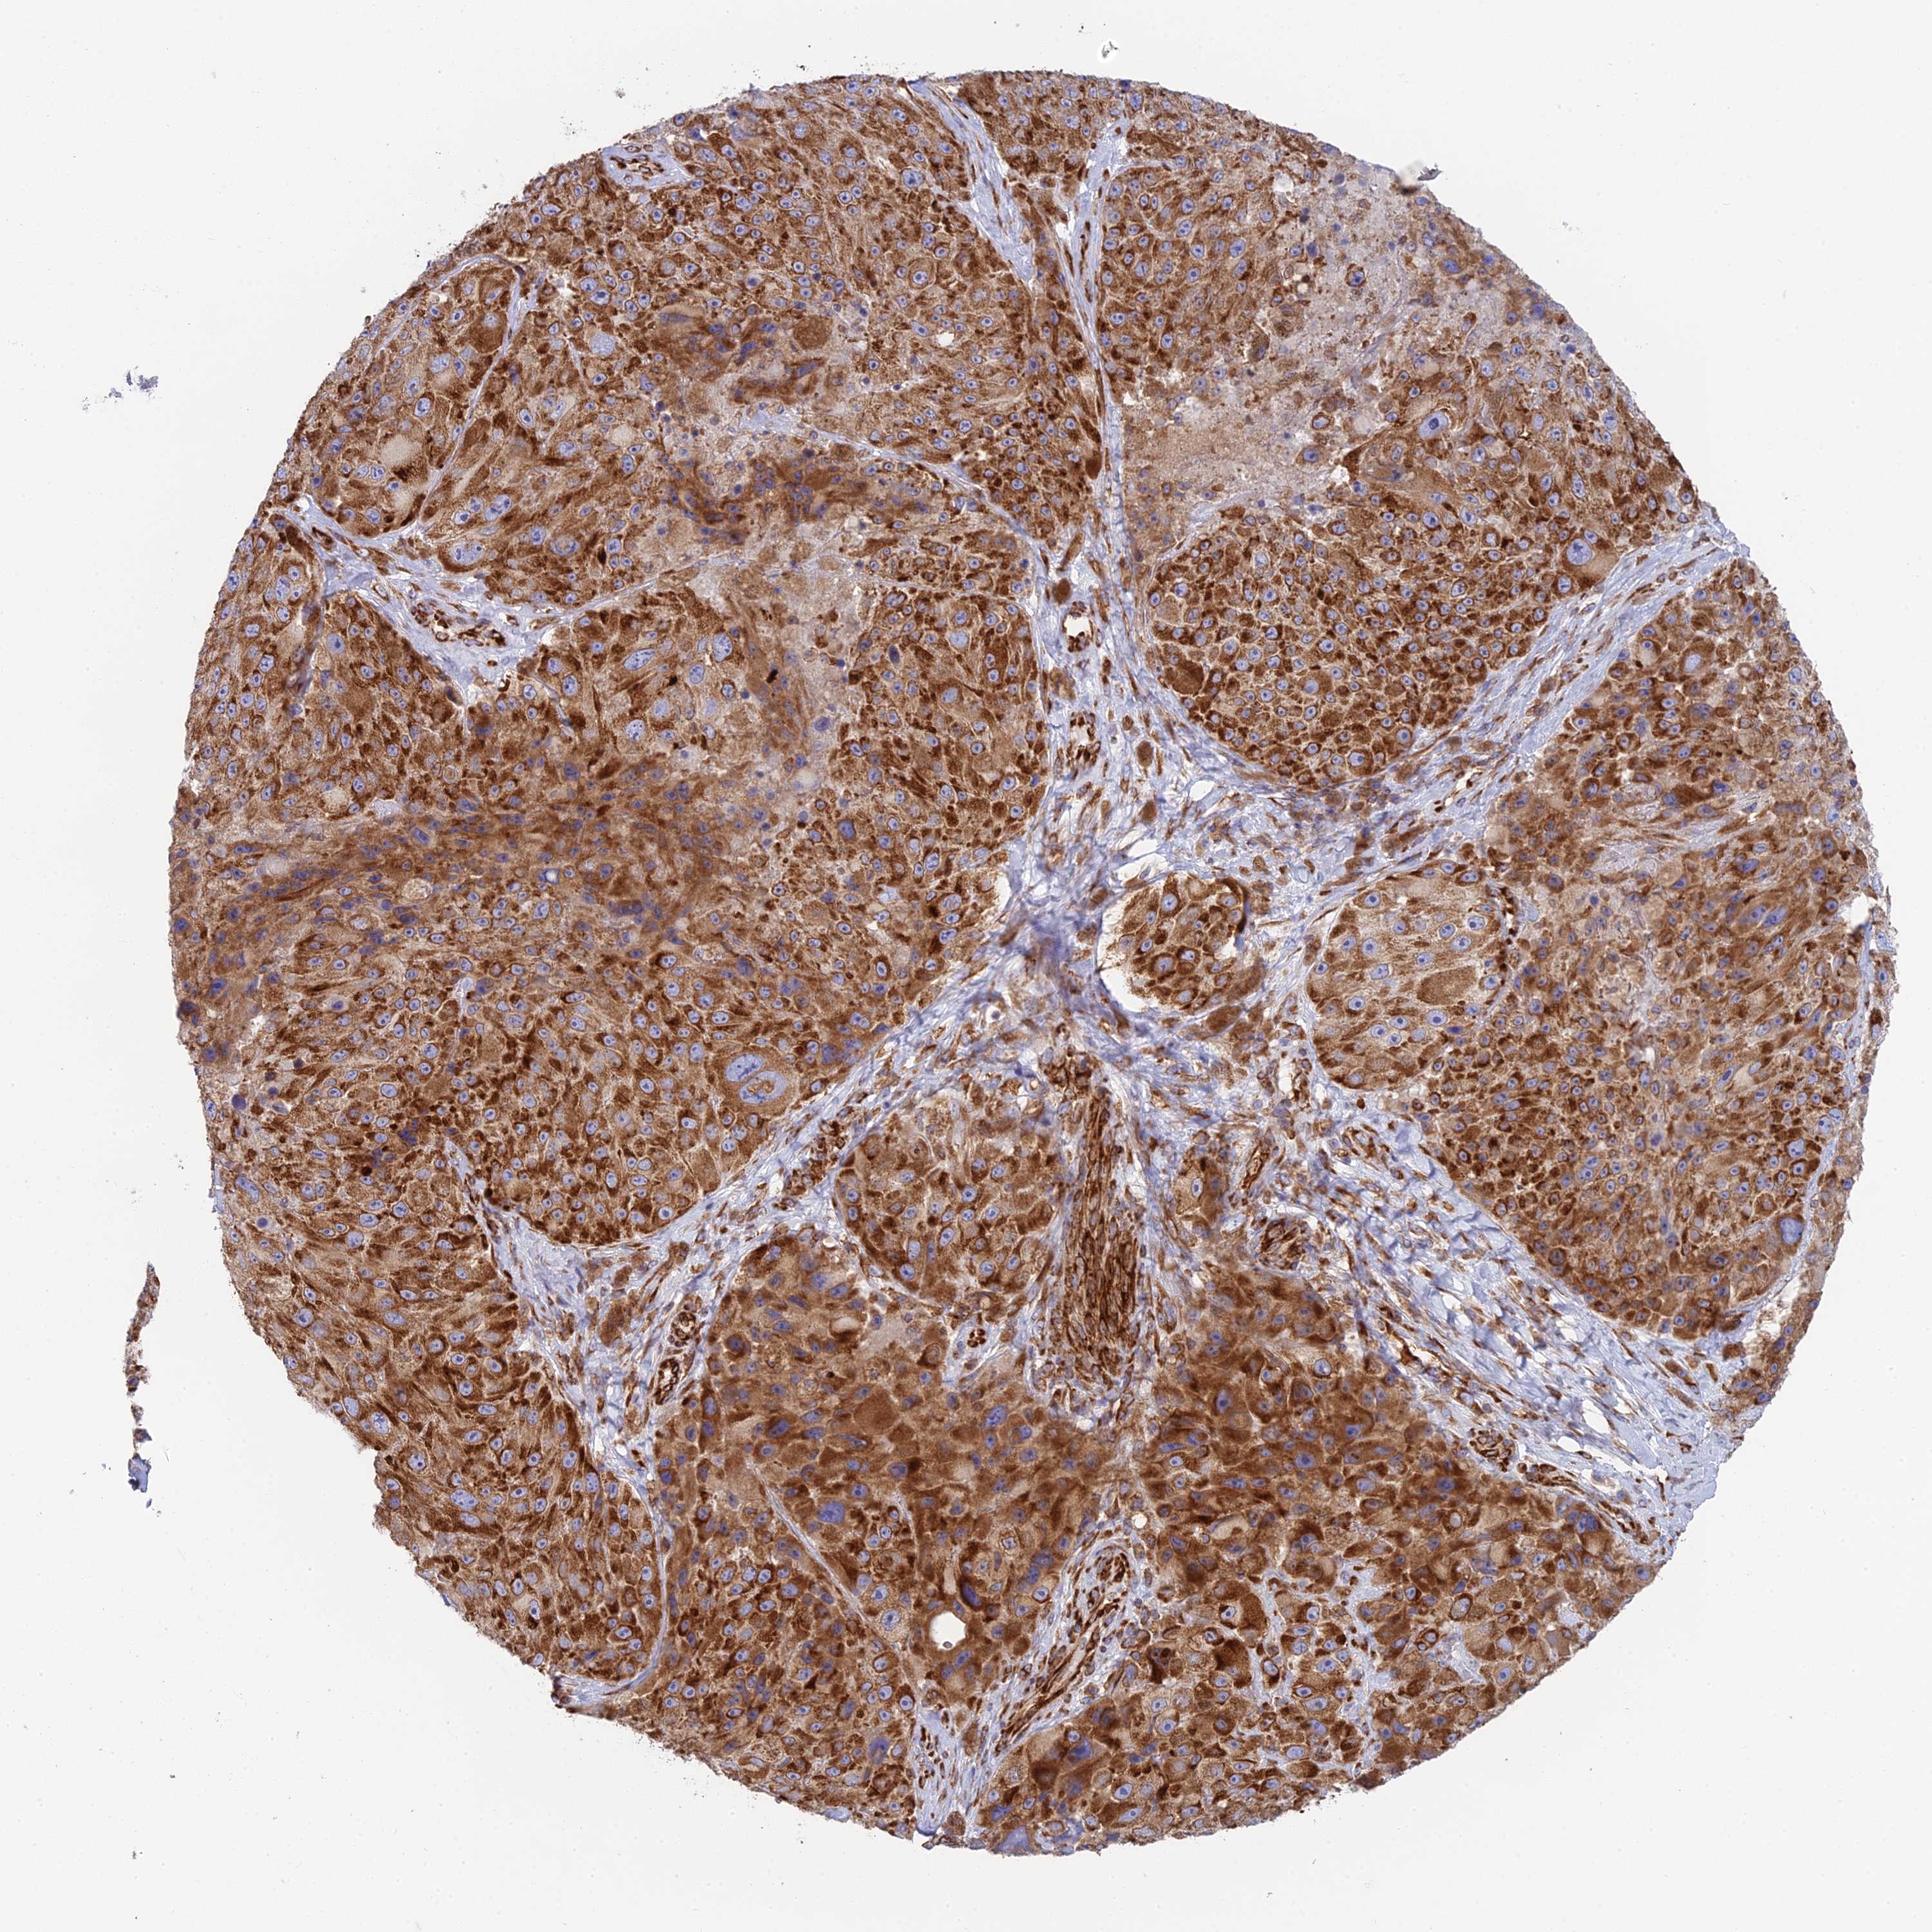

MELANOMA - Protein expressioni

A mouse-over function shows sample information and annotation data. Click on an image to view it in a full screen mode. Samples can be filtered based on level of antibody staining by selecting one or several of the following categories: high, medium, low and not detected. The assay and annotation is described here.

Note that samples used for immunohistochemistry by the Human Protein Atlas do not correspond to samples in the TCGA dataset.

Antibody stainingi

Antibody staining in the annotated cell types in the current human tissue is reported as not detected, low, medium, or high, based on conventional immunohistochemistry profiling in selected tissues. This score is based on the combination of the staining intensity and fraction of stained cells.

Each image is clickable and will lead to virtual microscopy that enables deeper exploration of all samples and also displays staining intensity scores, fraction scores and subcellular localization as well as patient and tissue information for each sample.

Antibody HPA043648

Staining

High

Medium

Low

Not detected

Intensity

Strong

Moderate

Weak

Negative

Quantity

>75%

75%-25%

<25%

None

Location

Nuclear

Cytoplasmic/membranous

Cytoplasmic/membranous,nuclear

Malignant melanoma, NOS

Malignant melanoma, Metastatic site